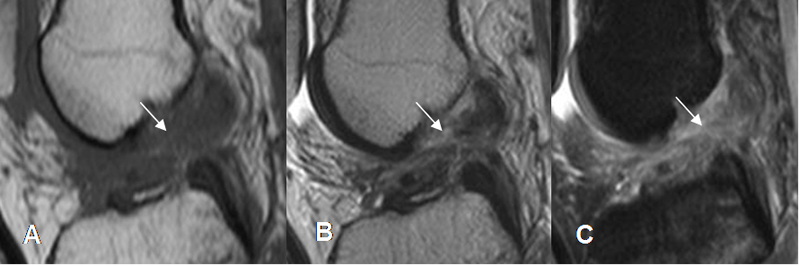

Fig 94. Ruptura aguda del LCA.

A: RM sagital en T1, B: RM sagital en T2 y C: RM sagital en STIR. No visualización del LCA, con cambios inflamatorios agudos, por ruptura reciente.